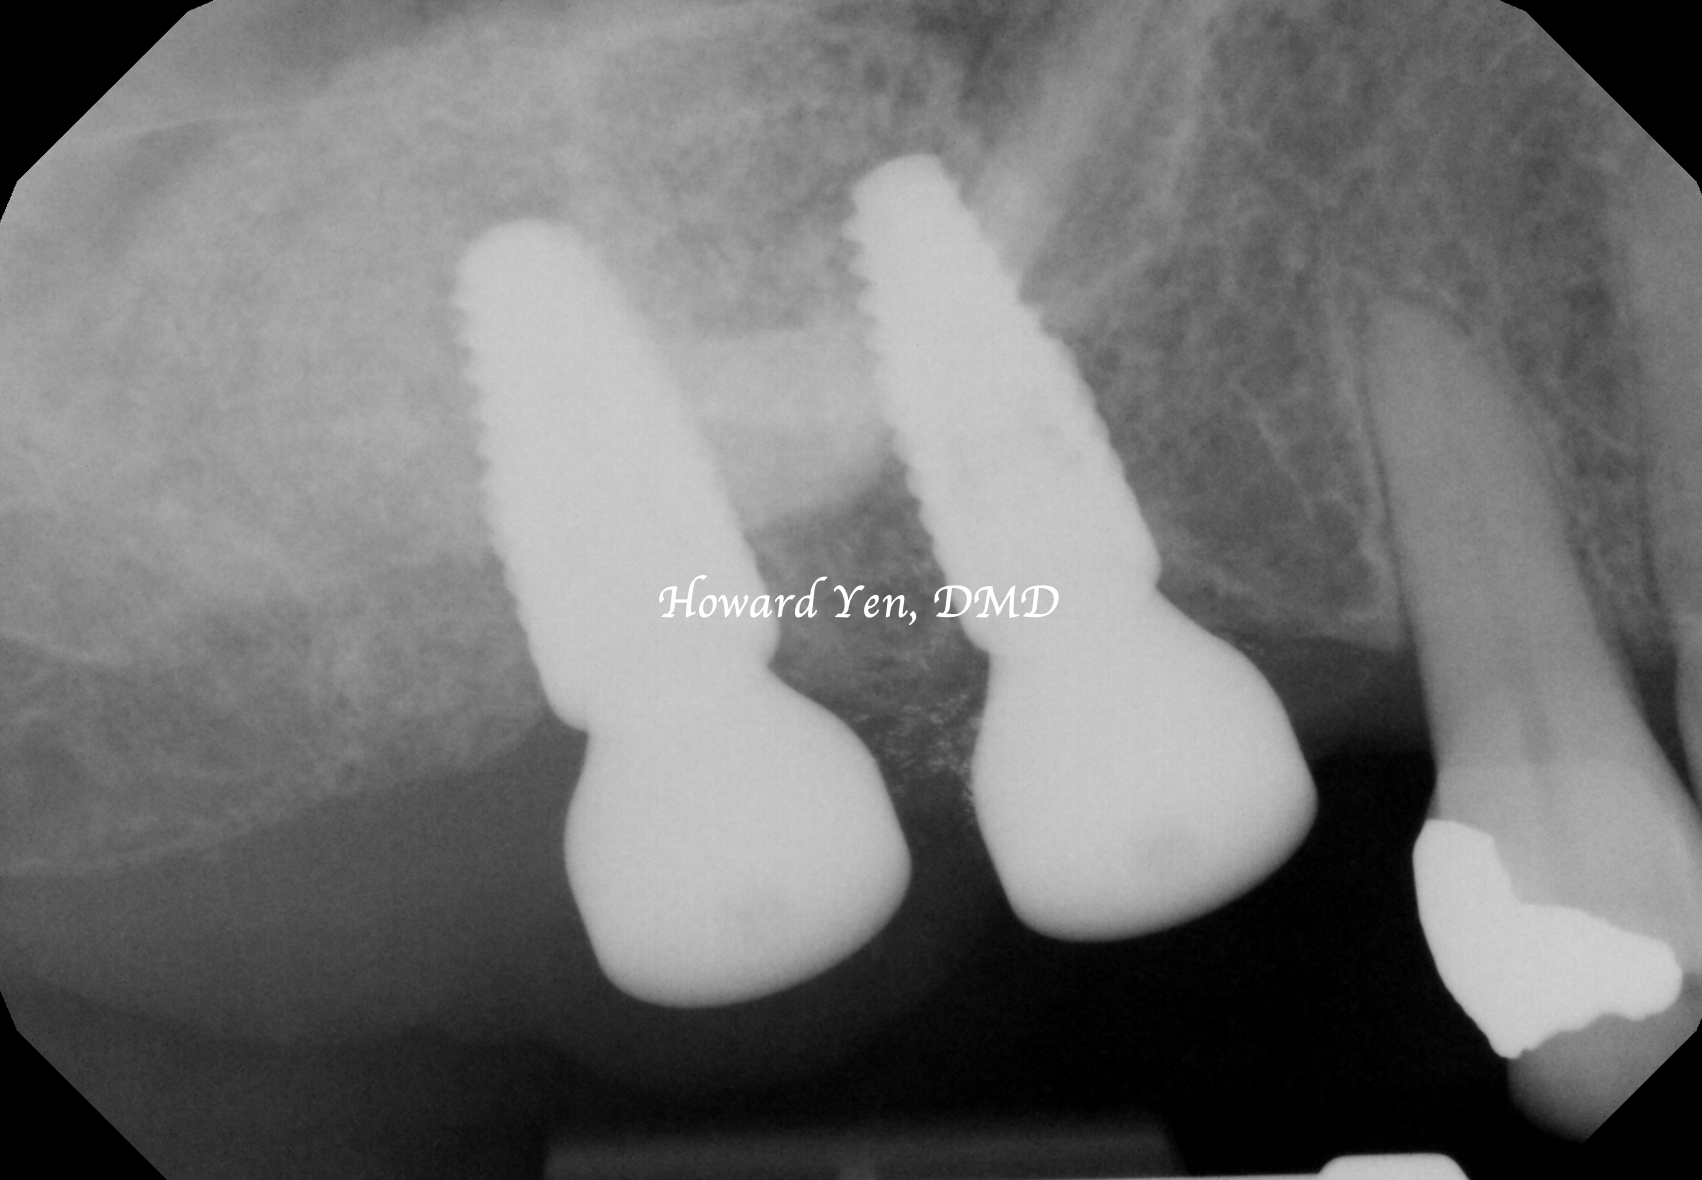

Depending on the amount of bone graft volume needed, dental implant can sometimes be placed simultaneously with sinus lift bone graft to help patient in reducing the overall treatment & healing time.